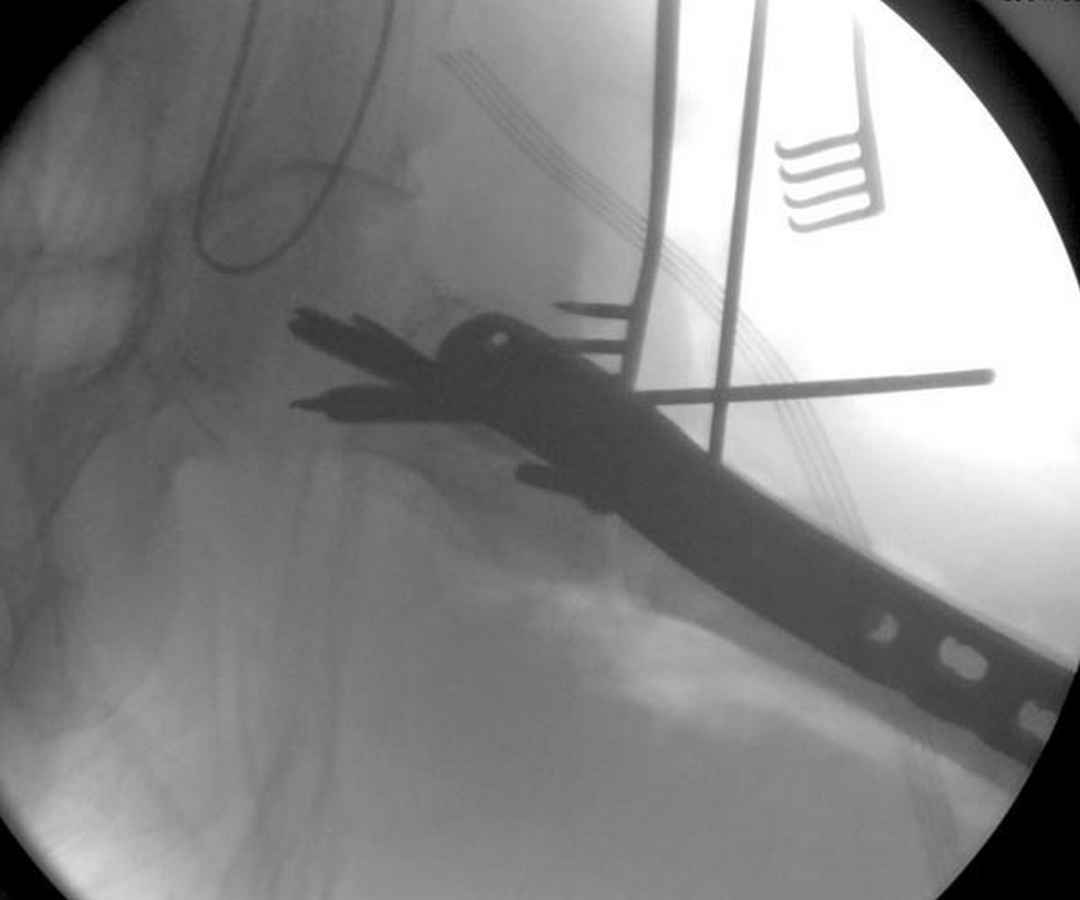

А вот к данным операциям без рентгена, как советует специалисты, я бы отнесся скептически, как раз здесь можно натворить много ошибок, например, от неправильной установки гвоздя мимо шейки до неудовлетворительной репозиции.

Из фиксаторов, мы бы применили цефаломедуллярные, потому что они "по закону моментов" из-за короткого рычага от центра головки к диафизу и по принципу "головка диафиз" механически лучше выдерживают нагрузки, чем пластины.

Здесь пара случаев фиксации похожих переломов:

первый высокоэнергетическая травма 36 лет